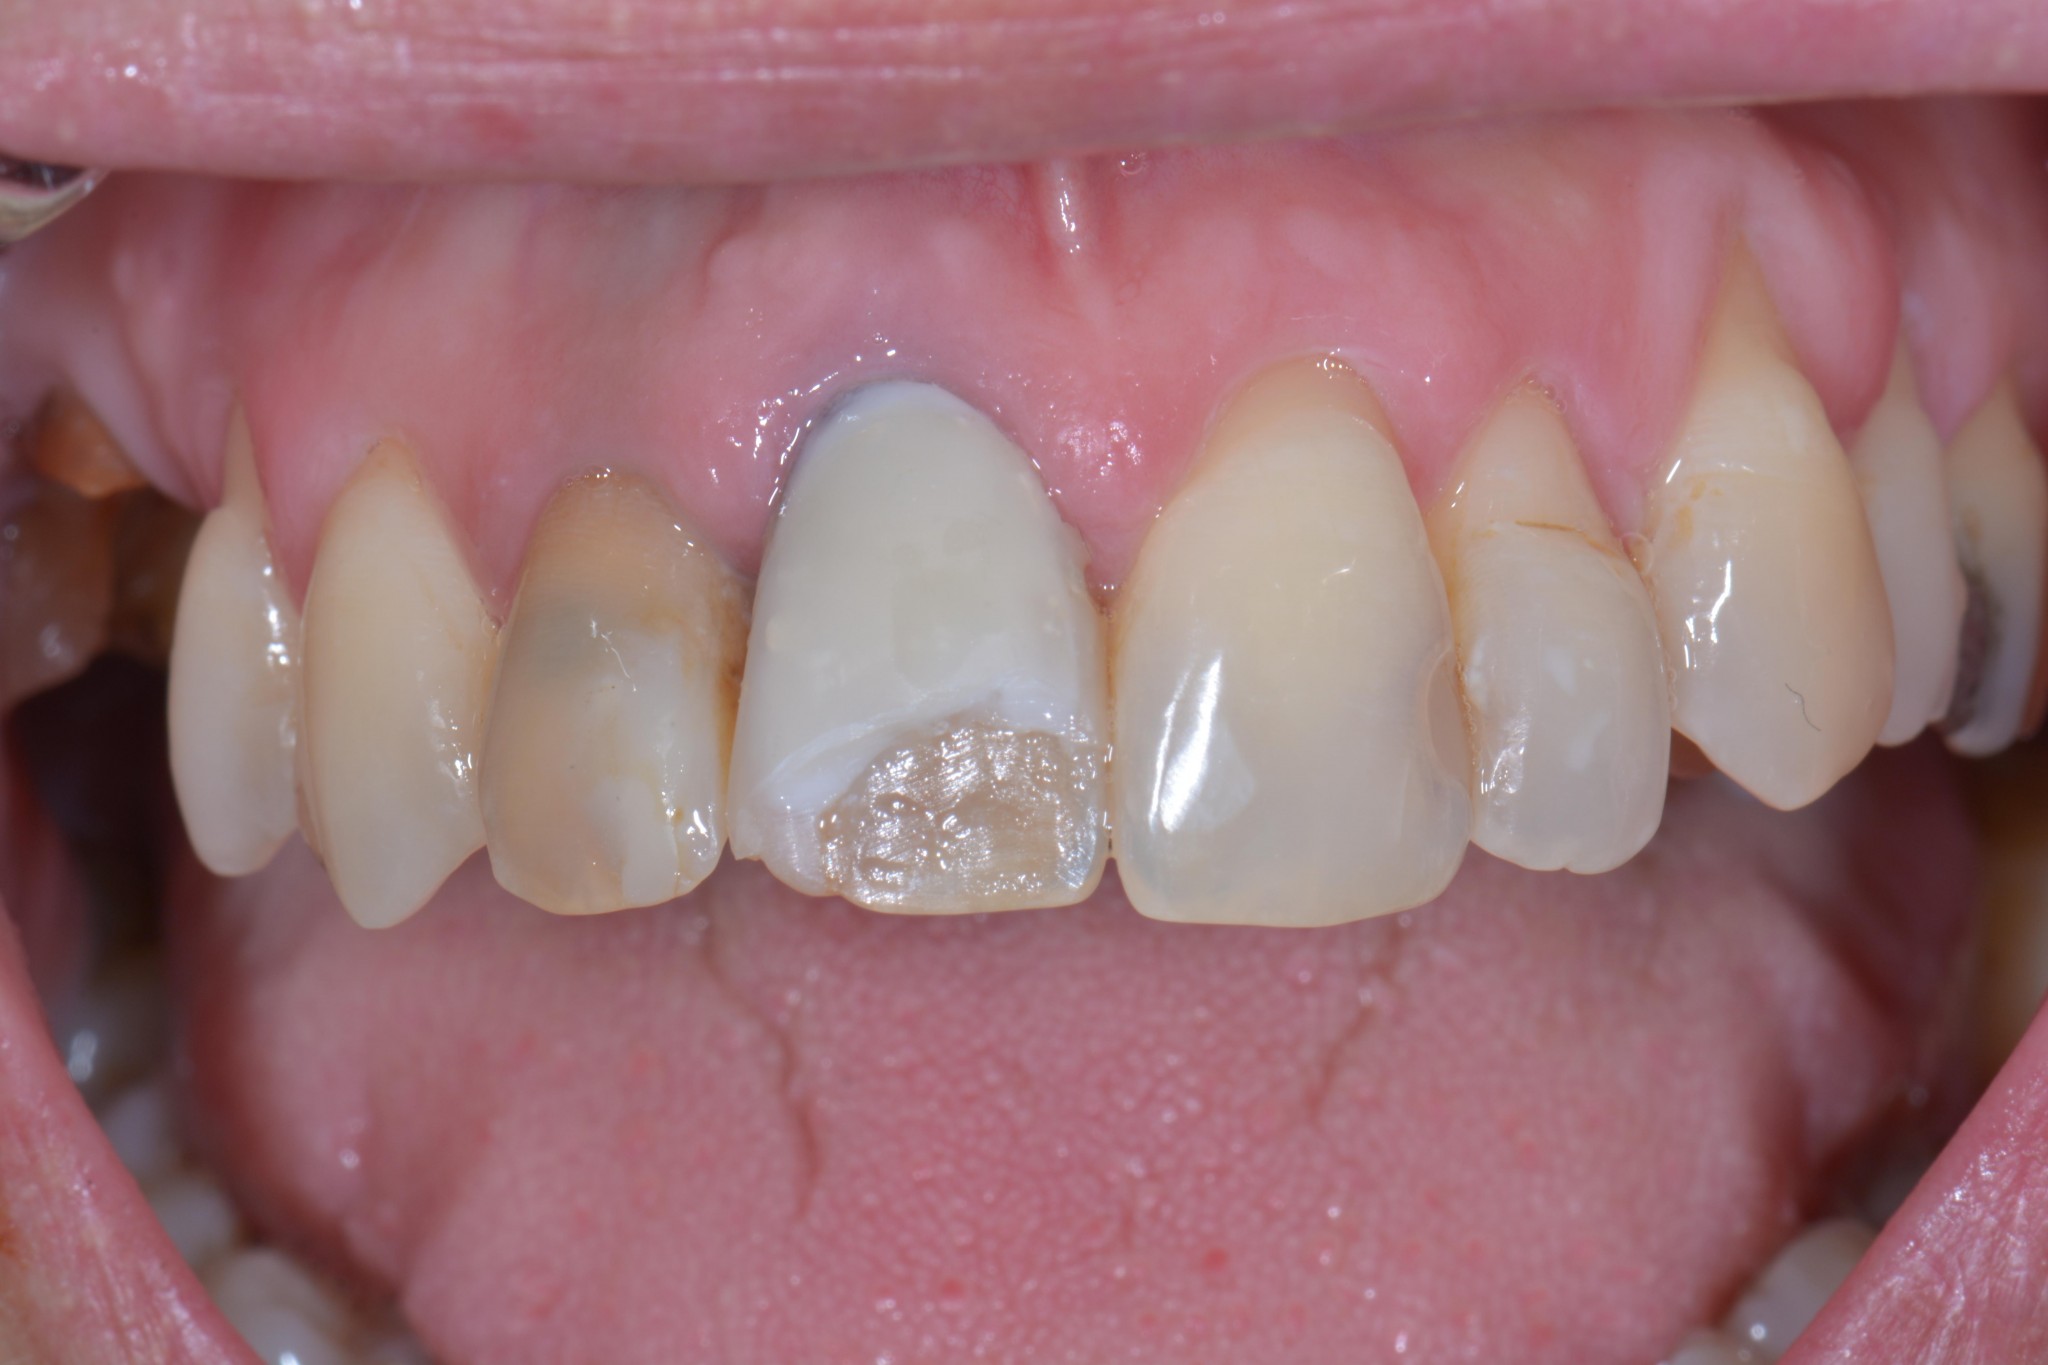

Ma l’hai vista la foto di prima?! Forse non ti è chiaro…cerco di spiegarti meglio…

Devo soffermarmi su cosa non vada in questo lavoro? Ma solo io ho pazienti che non accetterebbero mai un lavoro simile? Per far pagare una merdata simile 250 euro in nero ci va un bel coraggio! Ma come dormi la notte? Ah, lo so, su un cuscino e un materasso imbottito di banconote belle soffici…

Il dente della signora aveva un perno dentatus a vista dal lato palatino, era discromico, è stato lasciato il vecchio composito sotto la nuova pregiata faccetta, ha il colore sbagliato e andava fissato un appuntamento di revisione per decenza prima di chiedere 250 euro. E poi il 21 ha una carie, il 12 è devitalizzato e deve contenere all’interno una di quelle schifezze di paste di medicazione nere. Il 15 e il 16 anche solo facendo aprire la bocca alla paziente si vede che hanno qualcosa che non va e la paziente mi ha detto “ah, sì, quello mi ha fatto malissimo e il dentista ha detto che la prossima volta vediamo un po’ se si riesce a recuperare, ho già un appuntamento ma a questo punto non vado più e vengo da voi…”